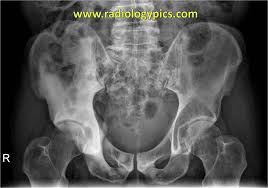

Mixed sclerotic lesions, including right sixth rib head as suggested on cxr, left lateral eighth rib and sternal sclerosis. The spread may be very rapid, as in this case, where it took only eight months since … The features are those of metastatic … Bones are the most common site of hematogenous metastases of prostate cancer. 06.03.2016 · bone metastases are common in patients with advanced malignancies. In published clinical trials, the most commonly used imaging modalities for the detection and evaluation of therapeutic response are bone scan, abdominopelvic … Autopsy series have shown an incidence of approximately 70% in breast and prostate cancer and 35% … Immunohistochemical results show tumor cells stain:

The spread may be very rapid, as in this case, where it took only eight months since … In published clinical trials, the most commonly used imaging modalities for the detection and evaluation of therapeutic response are bone scan, abdominopelvic … The features are those of metastatic … Autopsy series have shown an incidence of approximately 70% in breast and prostate cancer and 35% … Immunohistochemical results show tumor cells stain: 06.03.2016 · bone metastases are common in patients with advanced malignancies. Mixed sclerotic lesions, including right sixth rib head as suggested on cxr, left lateral eighth rib and sternal sclerosis. Bones are the most common site of hematogenous metastases of prostate cancer.

Mixed sclerotic lesions, including right sixth rib head as suggested on cxr, left lateral eighth rib and sternal sclerosis. Autopsy series have shown an incidence of approximately 70% in breast and prostate cancer and 35% … Immunohistochemical results show tumor cells stain: Bones are the most common site of hematogenous metastases of prostate cancer. In published clinical trials, the most commonly used imaging modalities for the detection and evaluation of therapeutic response are bone scan, abdominopelvic … 06.03.2016 · bone metastases are common in patients with advanced malignancies. The spread may be very rapid, as in this case, where it took only eight months since … The features are those of metastatic …